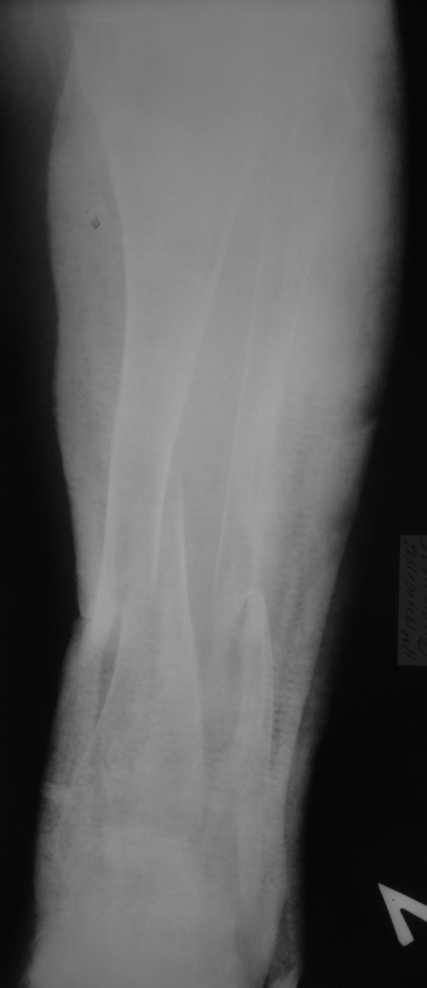

Уважаемые коллеги! Здравствуйте! Прошу у Вас совета вот по какому случаю.В нашу клинику поступила женщина 71 год. Травма в результате ДТП. (Пациентка передвигалась на инвалидной каляске и была сбита автомобилем). Диагноз: Множественная травма. Перелом нижней трети правого бедра. Перелом средней трети правой б/берцовой, малоберцовой кости, нижней трети левой большоберцовой, м/берцовой кости.Травматический шок. Со стороны внутренних органов и систем без патологии. Больная госпитализирована в реанимационное отделение, где было наложено двойное скелетное вытяжение за правую н/конечность. Левая н/конечность иммобилизована гипсовой лонгетой. Из анамнеза: больная является инвалидом 1 группы по опорно-двигательному аппарату. В детстве перенесла рахит. Осложнением которого "О" образная деформация нижних конечностей. Ограничено отведение нижних конечностей, деформирующий артроз тазобедренных и коленных суставов. В 1990 году перелом правого бедра остеосинтез пластиной. После операции больная передвигалась только на костылях или в инвалидной коляске.

Прошу прощения за качество снимков. Р-графия производилась в реанимационном отделении передвижным аппаратом.

Но даже при малоинвазивной методике лечения применимой для даной больной существуют следующие проблемы: выраженный остеопороз, тонкий кортикал, очень широкий канал.

Проблема в том, что в сагитальной плоскости угол голеней =30 градусам. Ширина канала 30.